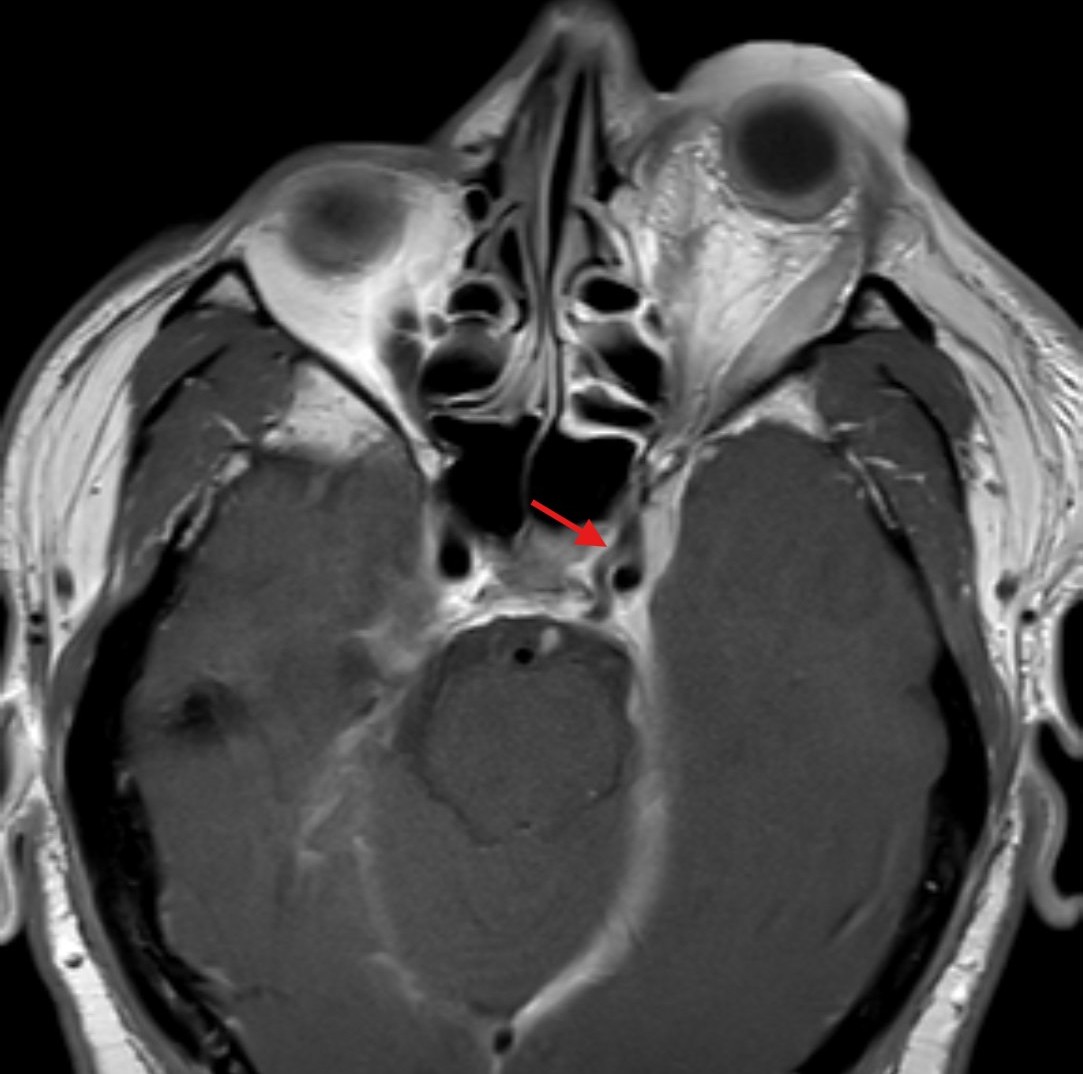

Orbital compartment syndrome (OCS) is an ophthalmologic emergency due to an acute rise in intra-orbital pressure and can result in permanent vision loss, oftentimes requiring emergent surgical decompression. Orbital compartment syndrome most commonly occurs due to recent trauma and is often easily diagnosed by history and physical exam. However, there are other causes of OCS where a more subacute/chronic rise in pressure can lead to an atypical presentation. This is a case report of a 48-year-old male who presented with left eye pain and swelling for the past 6 months. The patient had seen two ophthalmologists prior to his emergency department (ED) presentation who had prescribed him an antibiotic ointment, oral steroids, and steroid eye drops. The physical exam in the ED was concerning for increased intra-ocular pressure (IOP) and decreased vision. Ophthalmology was consulted and requested magnetic resonance angiography (MRA) to assess a vascular etiology given tortuous retinal vasculature. Emergent surgical decompression was deferred due to chronicity of symptoms, and patient was started on dorzolamide/timolol and brimonidine eye drops as well as intravenous (IV) acetazolamide with subsequent improvement in IOP. Imaging revealed a left carotid-cavernous sinus fistula (CCF), and the patient was admitted to neurosurgery. Patient successfully had an embolization with subsequent normalization of IOP and improvement of symptoms. This case is a good example of how non-traumatic causes of OCS can lead to misdiagnosis and how surgical decompression could potentially be deferred in subacute OCS.